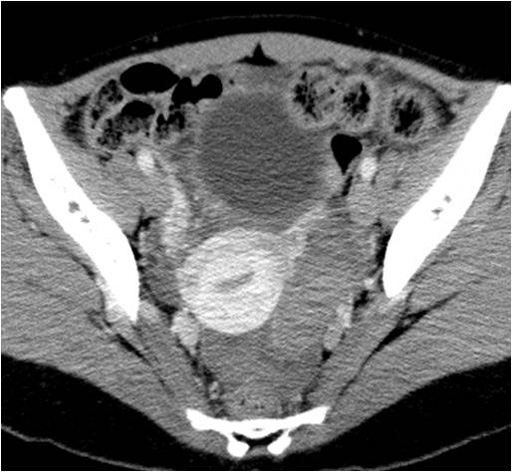

No.87症例5:29才女性

下腹部痛

安静時に突然の下腹部痛が出現し、当院救急外来受診となった。

WBC 5250 /μl、RBC 347x104 /μl、Hb 7.4 g/dl、Hct 25.1 %、Plt 27.8x104 /μl、CRP 0.60 mg/dl、その他特記すべき異常なし。

• 図1 単純CT

• 図2 単純CT